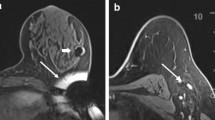

Radar localisation involved the SCOUT Surgical Guidance System (Merit Medical Systems, Inc. South Jordan, UT), a radar reflector and an infrared light-emitting probe that guides the surgeon to the lesion. It consists of a 12-mm fiducial reflector preloaded into a 16-gauge introducer needle, and a console and handpiece system, which localises the reflector. The reflector contains an infrared light receptor, transistor switch, and two nitinol antennae. The handpiece generates an audible signal when positioned over the reflector. Preoperative localisation involved percutaneous insertion of the reflector into the breast after local anaesthesia and under ultrasound guidance by an interventional breast radiologist. The reflector was deployed adjacent to or within the targeted lesion or adjacent to the clip. Post-procedure mammogram confirmed satisfactory placement of the reflector (Fig. 1).2,3,13,14,15,16